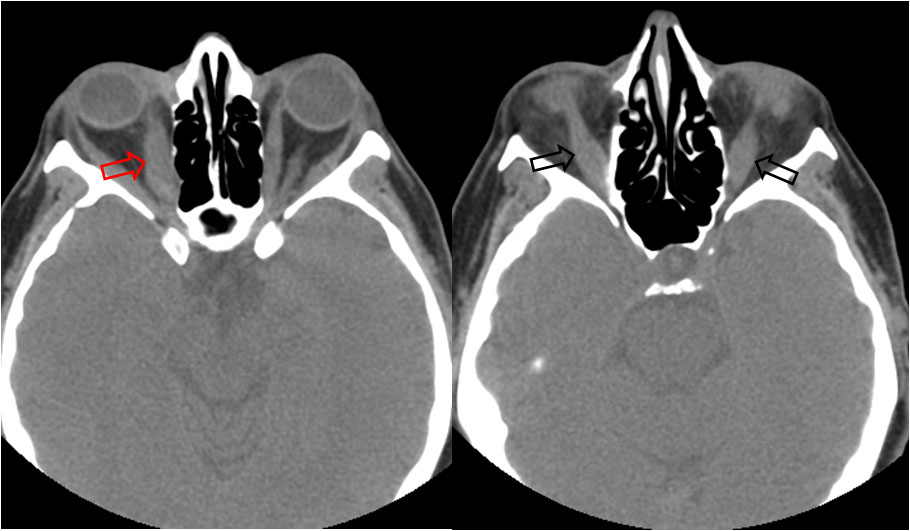

Singo visible en el estudio de órbitas con TC o RM y que se refiere a la apariencia que adoptan los músculos orbitarios en la orbitopatía tiroidea, más comúnmente causada por enfermedad de Graves.

La afectación muscular provoca un engrosamiento de los vientres musculares pero respeta la inserciones tendinosas en el globo ocular, por lo que esta forma del músculo recuerda a la botella del refresco.

Este signo permite diferenciar la enfermedad de Graves del pseudotumor orbitario, en el que también existe un engrosamiento de los músculos orbitarios pero que no respeta las inserciones tendinosas.

Los músculos más frecuentemente afectados son los rectos inferiores, seguidos de los mediales, superiores, laterales y, finalmente, los oblicuos.